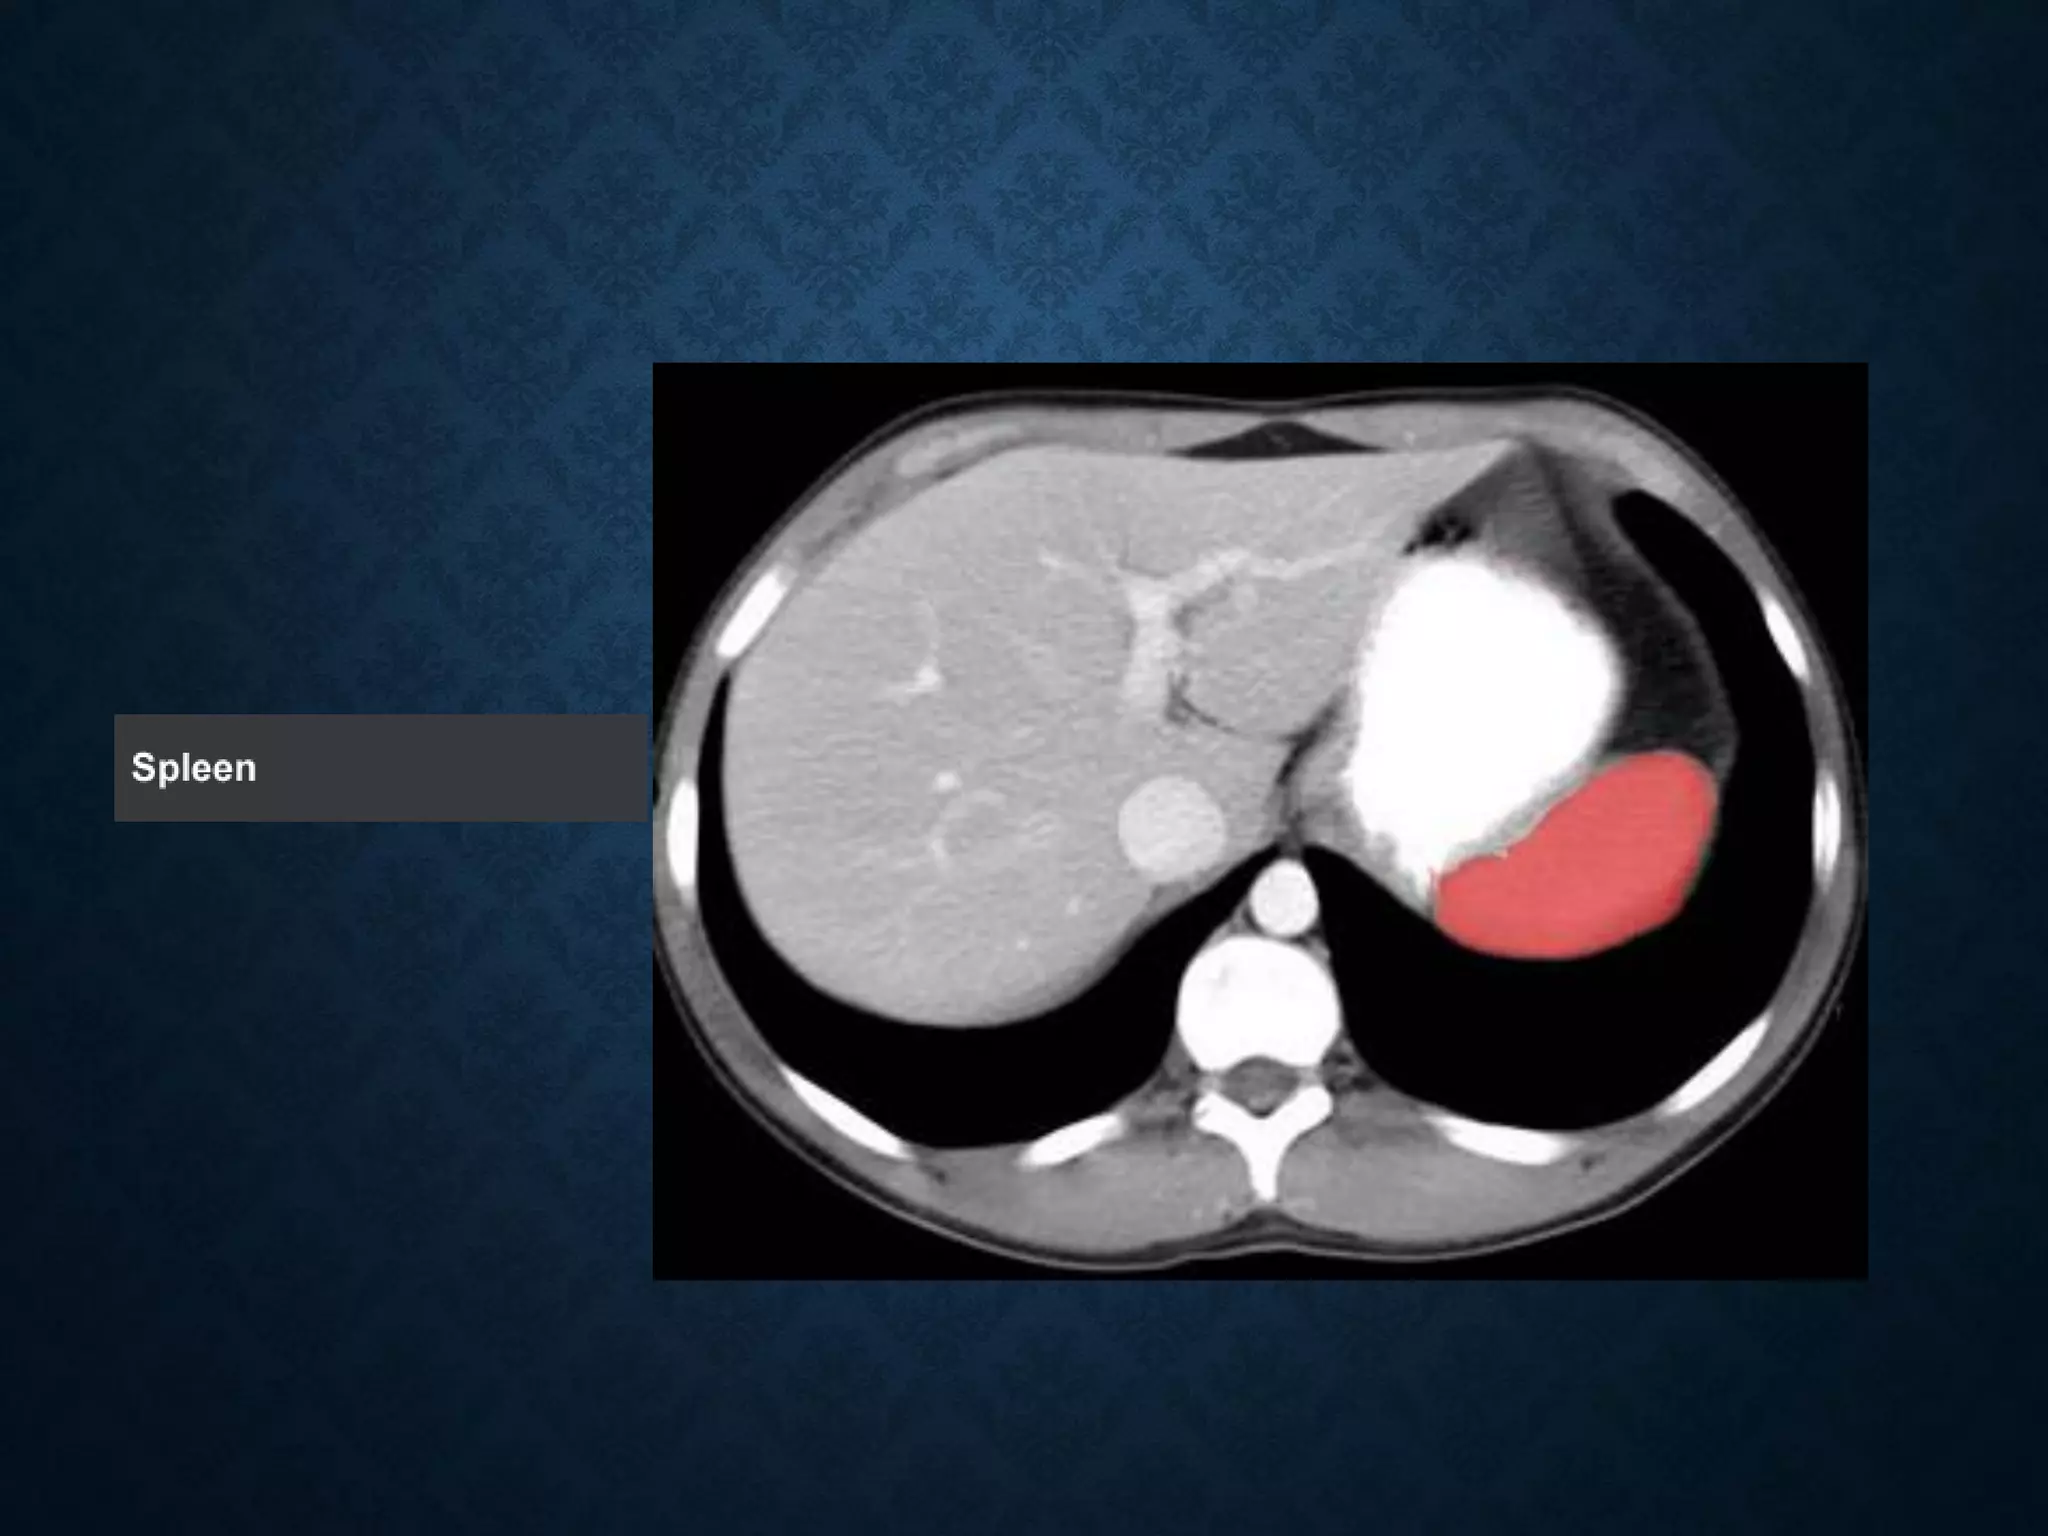

Identify the following structures in the body CT to the right. To view the location of the structure in the image click on

the label at the left and the structure will be indicated in the image. Abdominal CT scans typically begin just above

the diaphragm, so the first slice you see is of the lower chest.

Identify the followingstructures in the body CT to the right. To view the location of the structure in the image click on the label at the left and the structure will be indicated in the image. Abdominal CT scans typically begin just above the diaphragm, so the first slice you see is of the lower chest.